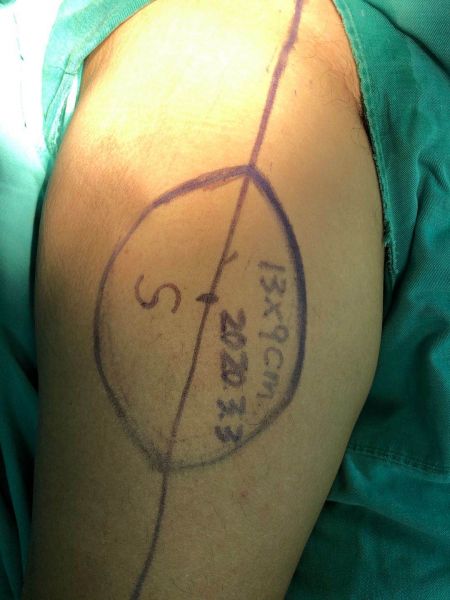

病例二:虎口挛缩,行虎口开大上臂外侧游离穿支皮瓣修补术